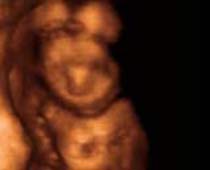

- Fetal Face Ultrasound Photos

- 3D Fetal Profile Ultrasound Scan Photos